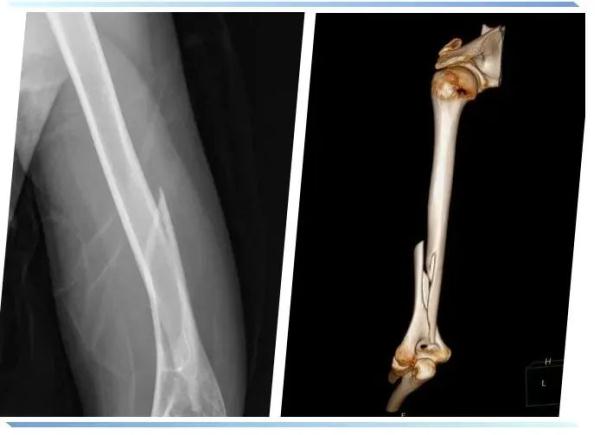

来到医院,骨科朱医生检查发现小周的情况属于左侧肱骨远端骨折,骨折线较长,需要通过手术治疗。不过一般这样的情况手术恢复效果不错,但是想要再次举起杠铃估计也要在半年后才可以。